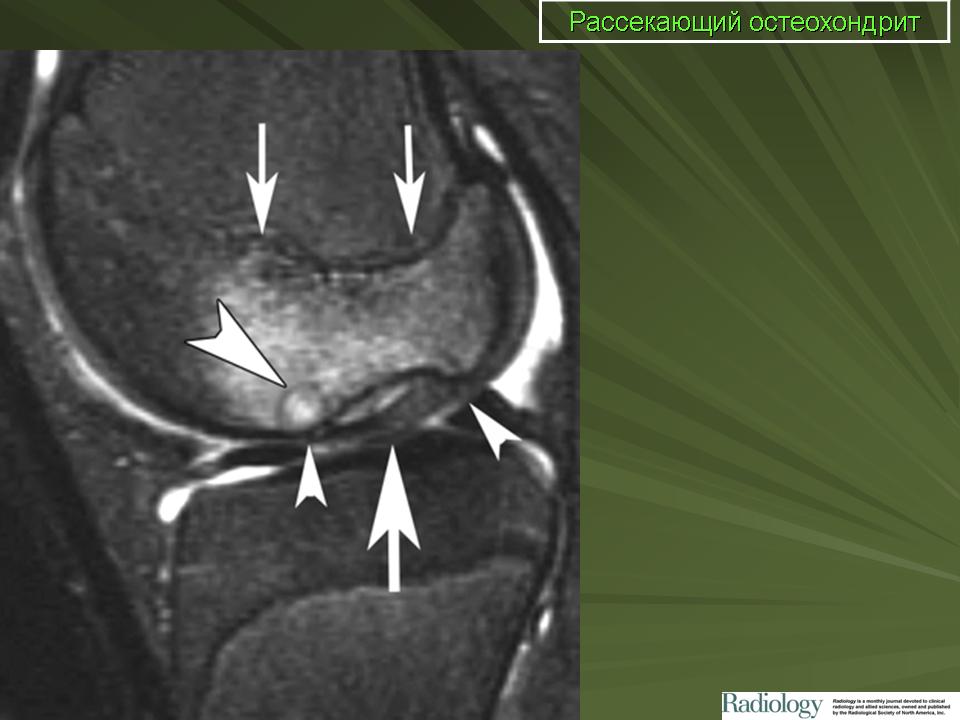

Рентгенологически в I стадии в субхондральной зоне выпуклой суставной поверхности мыщелка бедра выявляется ограниченный участок уплотнения кости. Обычно он двояковыпуклый, достигает размеров 1,0×1,5 см и ограничен узким ободком просветления. Затем (во II стадии) происходит отграничение уплотненного костно-хрящевого фрагмента от материнского ложа: расширяется зона просветления вокруг него, фрагмент начинает выступать в полость сустава (рис. 10). В III стадии определяется ниша в области суставной поверхности мыщелка бедренной кости, а внутрисуставное тело обнаруживается в любой части коленного сустава (обычно, в одном из заворотов, а при блокаде сустава - между суставными поверхностями).

МРТ.  Рассекающий остеохондрит

Рисунок 1: